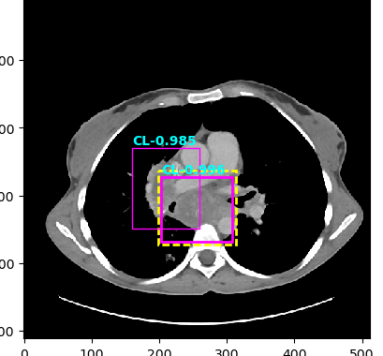

Figure 4: Six sample detection results are illustrated with the annotation lesion patches as yellow dashed boxes. The outputs from our proposed detection framework are shown in colored boxes with LiVer lesion (LV) in Red, Lung Nodule (LN) in Orange, ABdomen lesion (AB) in Green, Chest Lymph node (CL) in magenta and other MiXed lesions (MX) in blue. (a) Four lung lesions are all correctly detected; (b) Two lymph nodes in mediastinum is presented; (c) A Ground Glass Opacity (GGO) and a mass are detected in the lung; (d) An adrenal nodule; (e) Correct detections on both the small abdomen lymph node nearly aorta but also other metastases in liver and spleen; (f) Two liver metastasis are correctly detected. Three lung metastases are detected but erroneously classified as liver lesions .